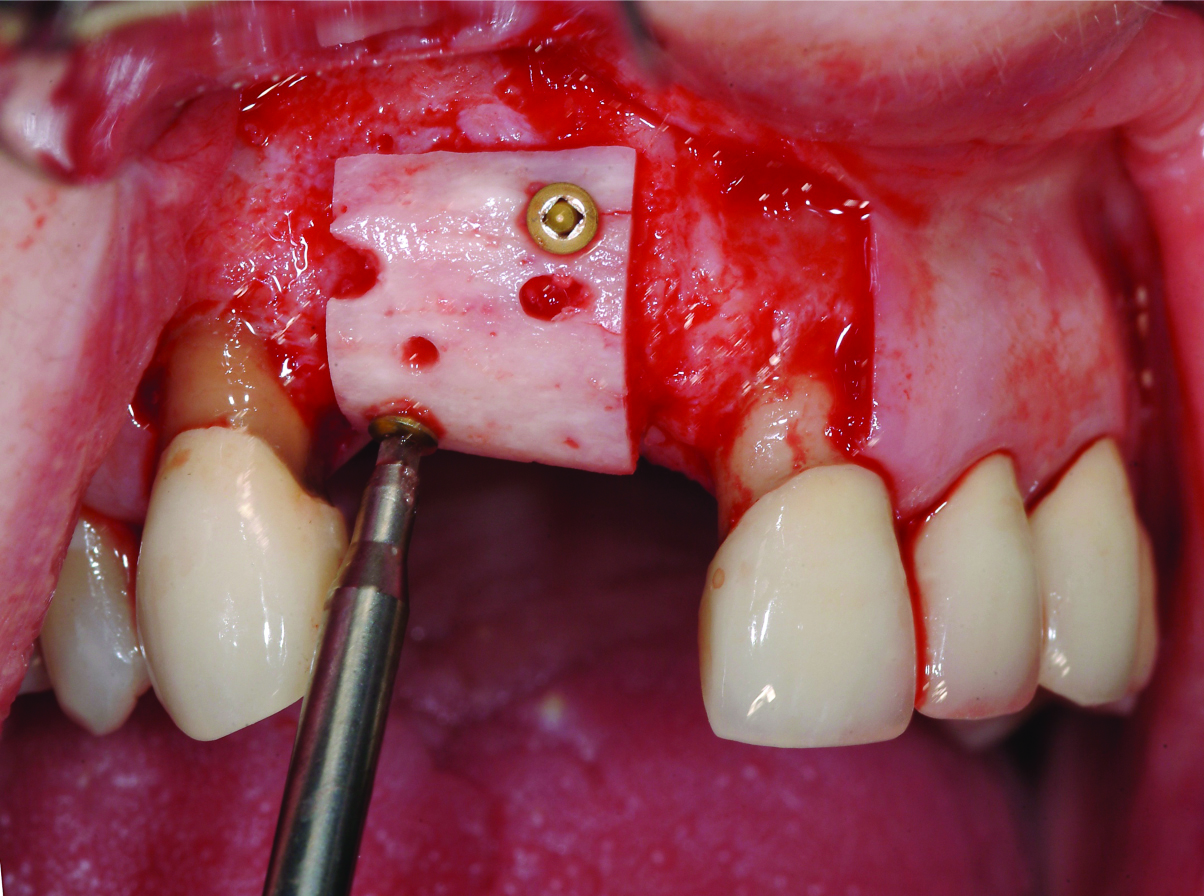

Fig 5. Insertion and stabilization of a shaped allogeneic block graft with fixation screws. Particulate allograft and an overlying resorbable membrane are subsequently adapted to the surgical site (not shown).

Figure 5

Where ridge preservation procedures are not possible or where the ridge is compromised by disease, ridge augmentation procedures are often required in the implant treatment plan, in order to allow restoratively driven implant placement. Autogenous bone grafts have been recognized as the material of choice, but many clinicians are increasingly using alternative materials to avoid a second surgical site and the morbidity that may be associated with procurement of the graft. Bone allografts in particulate form have long been used in periodontal therapy and in ridge augmentation for implant site development. Although not extensively researched, bone allografts in block form are now being used as alternatives to autogenous block grafts in the augmentation of more significant ridge defects.5-8 In Figure 5, a contoured allogenic corticocancellous block graft was stabilized with fixation screws, surrounded by particulate bone in the proximal voids and protected with a cross-linked collagen membrane. This case illustrates the similarity to conventional autogenous block graft procedures. A retrospective review of the results of the first 10 cases using this material alternative is promising, with bone volume gains similar to that achieved with autografts. Bone volume and its post-restoration stability can be influenced by implant design, with literature support for platform switching or micro-grooved implant collars.9-12 It is well-documented that 3-dimensionally correct implant placement is important, because this impacts bone stability in the postsurgical period.13